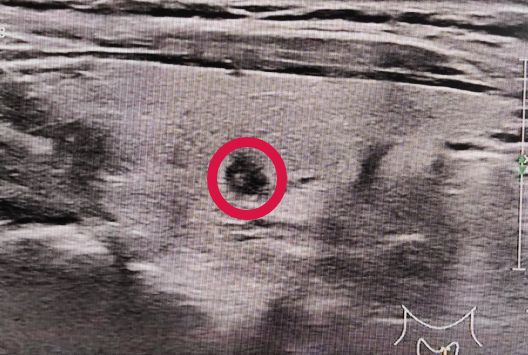

活检MM什么针功夫!_https://www.jmylbn.com_新闻资讯_第5张

▲超声:甲状腺肿瘤